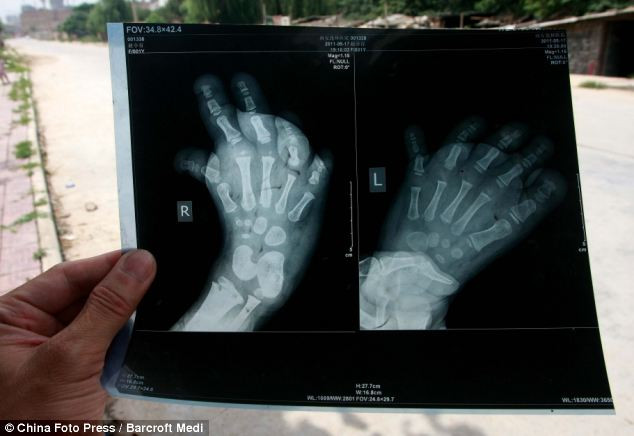

| Ảnh chụp X-quang cho thấy xương bàn chân của Ngọc đã bị biến dạng và có xu hướng cong lên. |